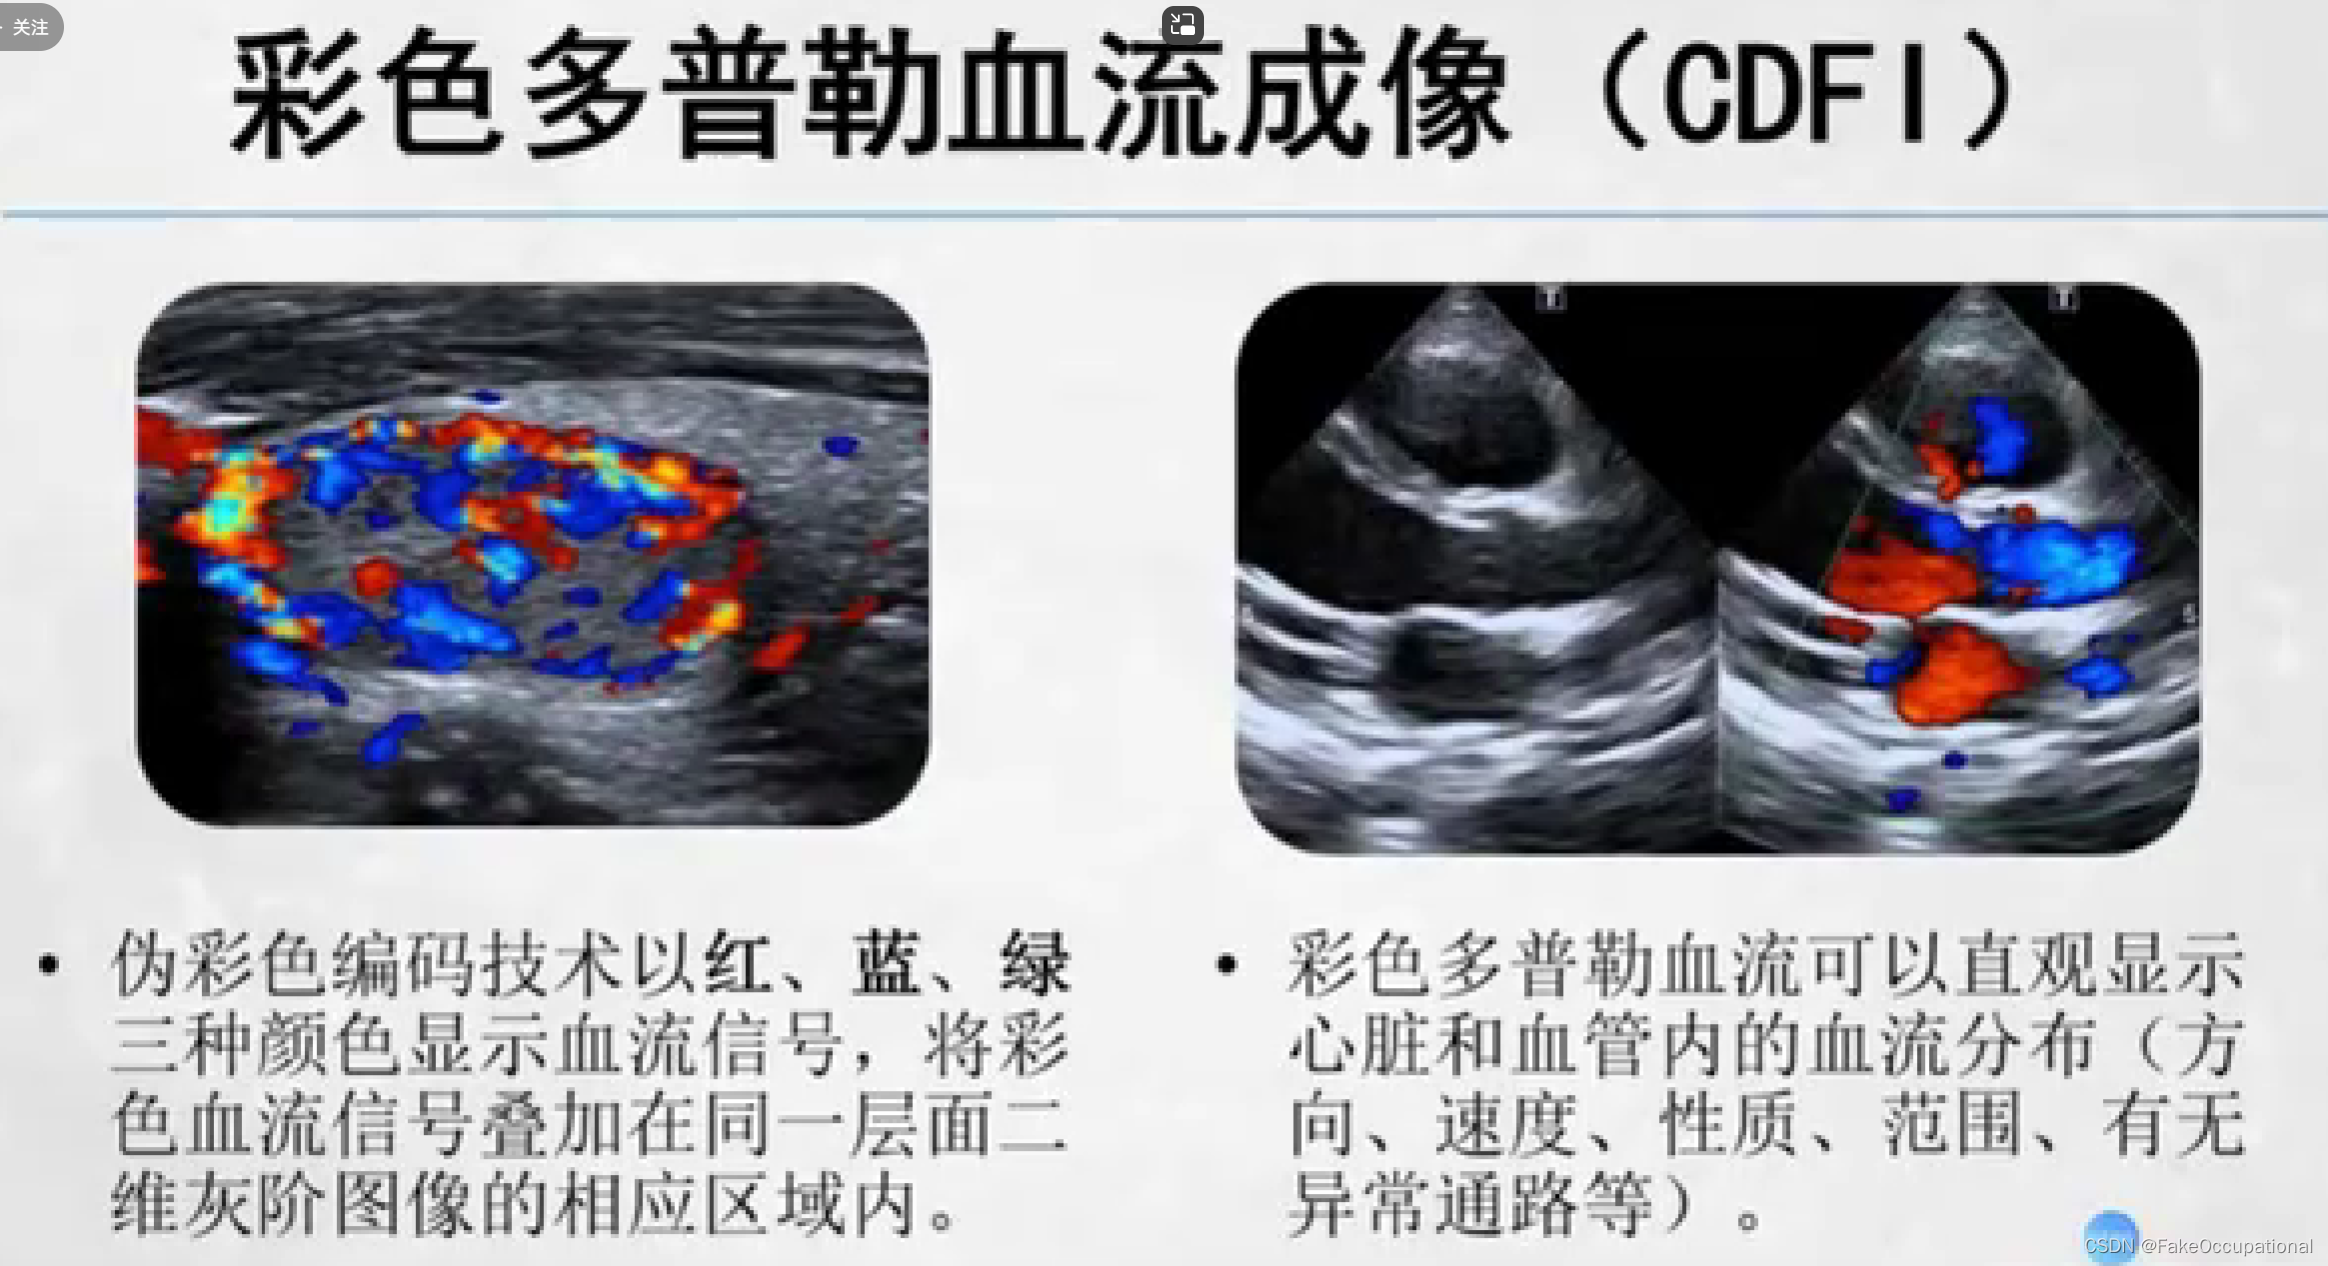

- 彩色编码实时显示血流方向、速度及血流性质:彩色多普勒血流成像(CDFI),彩色多普勒能量图(CDE)